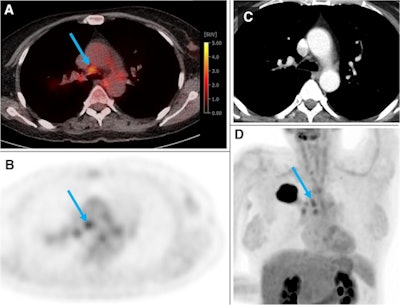

A 54-year-old woman from the training and test cohort with a G2 adenocarcinoma of the right upper lobe (44 mm). Several hilar and mediastinal lymph nodes showed higher F-18 FDG uptake than the normal liver (PET score of 3). The blue arrow depicts an N2 paratracheal lymph node with 7 mm short axis and SUVmax of 3.5. Based on visual assessment, N2 disease would be suspected in this case. According to the gradient boosting classifier model, the probability of N2/3 is only 0.17. The patient was confirmed to be N0 by ultrasound-guided transbronchial needle biopsy of the ipsilateral hilar, paratracheal, and subcarinal LNs. Image courtesy of the European Journal of Nuclear Medicine and Molecular Imaging through CC BY 4.0.The gradient boosting classifier model showed significantly higher AUC than the visual PET score in the training and test cohort (0.91 vs. 0.87, p = 0.003) and slightly higher AUC in the validation cohort (0.94 vs. 0.91, p = 0.23).